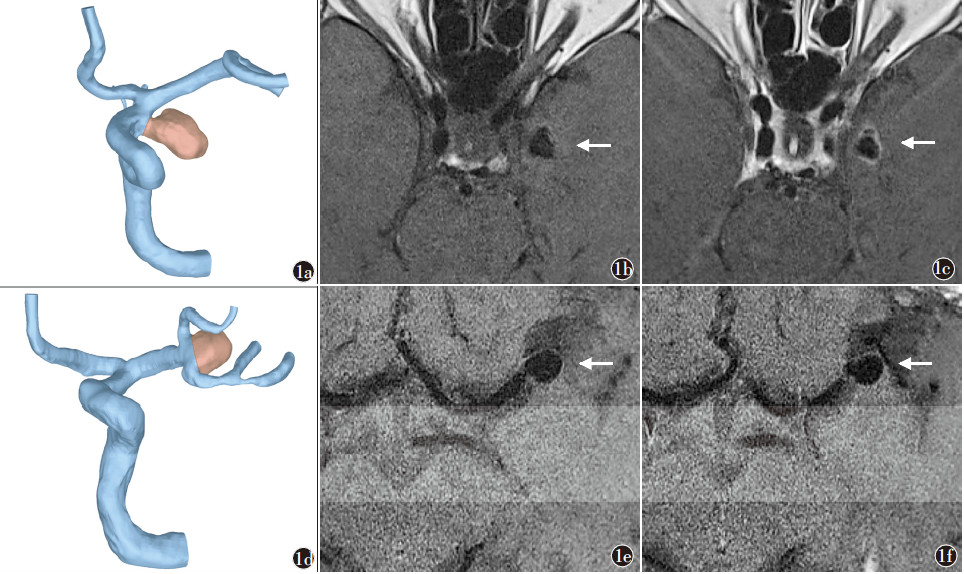

对于动脉瘤的破裂风险,另一个重要参数是“动脉瘤壁强化”,动脉瘤的变化主要是瘤壁,瘤壁的炎症是动脉瘤增长的真正动力;而高分辨MR可以直接观察动脉瘤壁强化程度。还有动脉瘤破裂风险量表等参数。